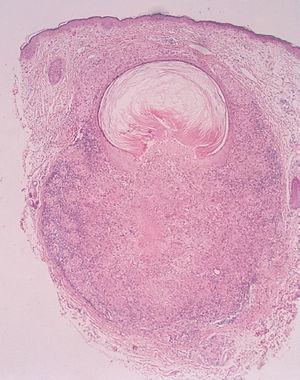

Los estudios de bioquímica sanguínea, hemograma y radiografía de tórax estaban dentro de la normalidad. La prueba de Mantoux fue negativa. El estudio histológico, que incluía los dos tipos de lesiones descritas, mostraba un granuloma tipo tuberculoide, bien definido, con necrosis central y un infiltrado de linfocitos alrededor de un pequeño quiste epidérmico roto. La necrosis caseosa estaba en contacto con el contenido del quiste (fig. 3). Se realizó otra biopsia de una pápula eritematosa, donde se observaba de forma aislada un granuloma tipo tuberculoide con necrosis central (fig. 4). La tinción de Ziehl fue negativa. Tras la exploración física, el estudio histológico y las pruebas complementarias para excluir otras enfermedades granulomatosas, se estableció el diagnóstico de LMDF.

Fig. 3.--Biopsia de una lesión de la figura 2. Se observa un granuloma tuberculoide con necrosis central, un infiltrado linfocítico en contacto con un quiste epidérmico roto y necrosis caseosa íntimamente asociada al contenido del quiste. (Hematoxilina y eosina, x4.)